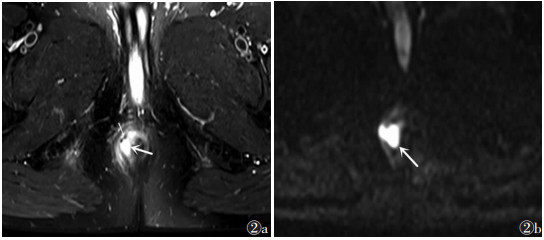

| 图 2 男,31岁,括约肌间复杂瘘管(Ⅱ级) 图 2a 轴位脂肪抑制T2WI显示内外括约肌间脓肿(粗箭)、内见点状气体信号影(细箭) 图 2b b值=1 000 s/mm2的DWI显示脓肿呈高信号 |

![]() |